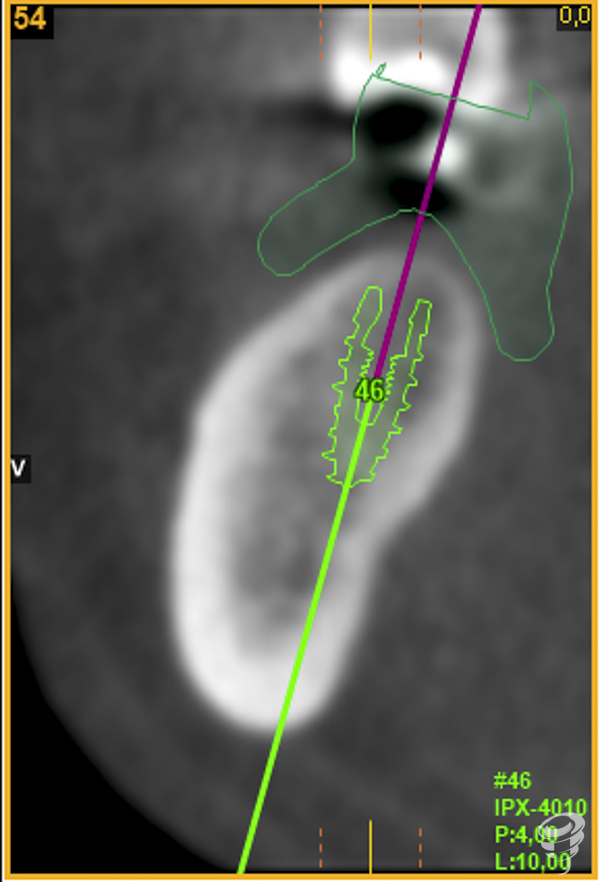

A.M.R Paciente de 40 años de edad, de sexo femenino, edéntula parcial, no fumadora y sin antecedentes médicos de interés. La paciente fue evaluada radiológicamente con una tomografía computarizada de haz cónico y se procedió a la planificación de su caso mediante el sistema informático Galimplant 3D Exacto®. Se planificaron dos implantes galimplant de 4X10mm (IPX 4010).

Una vez realizada la planificación de los dos implantes, se lleva a cabo la impresión de la férula quirúrgica dento-soportada con dos orificios cilíndricos adaptados a la fresa pin de 2 milímetros de diámetro. Esta fresa tiene la función de guiar tridimensionalmente la posición del implante.

A posteriori, se retira la guía quirúrgica y se realiza el fresado con la fresa Stop de 2 mm de diámetro y 14 mm de longitud directamente sobre los lechos implantarios. Esta fresa creará el lecho implantario idóneo (2 mm infra óseo) ya que el espesor mucoso en este caso es de 2mm.